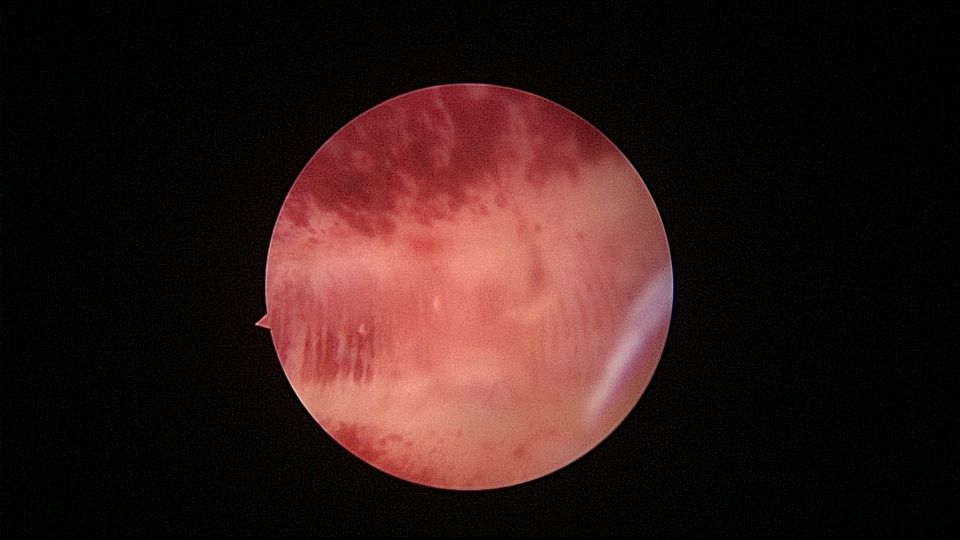

患者55岁,G1P1,顺产1次。安环34年,闭经半年,2天前外院取环失败,感下腹疼痛不适。术前复查B超,子宫前壁肌瘤直径4cm,宫内节育器回声。术中见子宫前倾后屈位,宫颈外口见息肉,镜鞘旋转扩宫进入宫腔,O型环位置正常,宫腔右前壁见直径2.5cm肌瘤结节突向宫腔,取环钩顺利取出节育环,宫腔无其他异常。该患者常规取环时未膨宫,子宫位置特殊,加之子宫受刺激后肌瘤凸向宫腔,可能对取环器械形成支点及杠杆效应,取环器械难以到达节育环位置,导致取环失败。